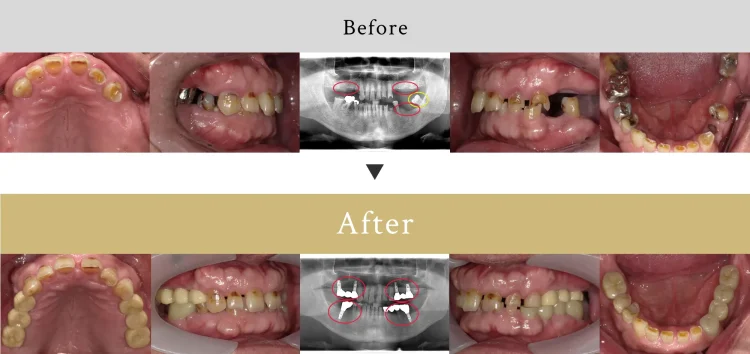

歯医者に40年以上通っておらず、歯がほとんど残っていない状態でした。また、この方は噛む力が非常に強く、食いしばりや寝ている時の歯ぎしりで歯が非常にすり減っていました。下の歯が上の歯茎に接触しており、このままインプラント治療を行うと悪い噛み合わせになりかねないため、骨を削り(骨整形)、インプラントを埋入するスペースを確保。患者様が金額を抑えた最小本数のインプラント治療をご希望されたため、一番奥の歯にはインプラントは入れず、またブリッジを併用したため合計6本のインプラントで治療を行いました。

これまで歯がほとんど残っていない状態でしたが、奥歯にインプラントを埋入し、上下の歯がしっかりと噛み合うように咬合再構成を行ったため、見た目はもちろん機能的にも大幅に改善することができました。